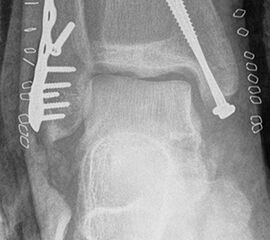

Frakturen vom Typ AO 44-C werden in der Regel mittels interfragmentärer Zugschraube und Neutralisations-Plattenosteosynthese versorgt. Die Versorgung von Frakturen mit metaphysärer Trümmerzone (AO 44-C2) ist mitunter anspruchsvoll. Entscheidend ist die Wiederherstellung der korrekten Länge und Rotation der Fibula. Die Verwendung von winkelstabilen Implantaten bietet hier eine höhere Stabilität. Bei Typ C Verletzungen liegt definitionsgemäß eine Syndesmoseninsuffizienz vor, die entsprechend versorgt wird (siehe Abschnitt Syndesmoseninsuffizienz). Bei hohen Fibulafrakturen (AO 44-C3, Maisonneuve-Frakturen) steht die Versorgung der Syndesmoseninstabilität im Vordergrund. Eine zusätzliche Versorgung der proximalen Fibulafraktur ist nicht erforderlich.

Die Versorgung instabiler Frakturen des medialen Malleolus erfolgt über einen leicht geschwungenen Zugang über den Innenknöchel nach distal verlaufend. Zunächst erfolgt die Exploration des medialen Gelenkanteils und des Frakturspaltes, um eingeschlagenes Periost und Kapselanteile, die eine anatomische Reposition verhindern können, zu entfernen. Anschließend erfolgt die Reposition der Fraktur. Es hat sich bewährt, dies mit einer Spitz-Spitzen-Repositionszange durchzuführen. Dafür erfolgt zunächst eine Bohrung im proximalen Fragment frakturnah um den einen Schenkel der Repositions-Klemme einzuhängen. Der zweite Schenkel wird unterhalb des medialen Malleolus durch das Deltaband eingebracht. Welches Osteosynthese-Verfahren für die Retention der Fraktur gewählt werden sollte, hängt von der Anzahl und Größe der Fragmente, dem Frakturverlauf und der Knochenqualität ab. Bei horizontalem Frakturverlauf und ausreichender Fragmentgröße erfolgt die Fixierung vorzugsweise mittels zweier Zugschrauben (Abbildung 13 & 14). Ist das Fragment zu klein oder handelt es sich um eine mehrfragmentäre Fraktur, so kann die Versorgung wahlweise mit einer Zuggurtungsosteosynthese oder mittels winkelstabiler Hakenplatte erfolgen. Diese Versorgungsarten bieten sich auch bei osteoporotischen Frakturen an.